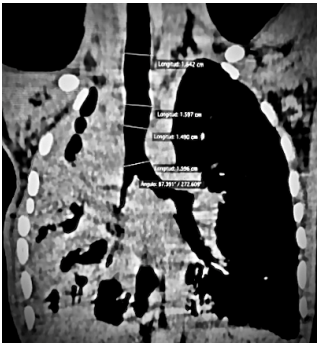

1,64, medio: 1,59; distal 1,59 cm (Figura 2); Serie esofagogastroduodenal con dilatación esofágica en tercio medio 3,24 cm, datos de dismotilidad esofágica (Figura 3). Ecocardiograma: dextroposición cardiaca secundaria a atelectasias. Broncoscopia: tráquea y bronquios con mucosa eritematosa friable y puentes de moco espeso purulento. Gammagrama pulmonar ausencia de ventilación y perfusión en pulmón derecho, pulmón izquierdo con perfusión y ventilación irregular.

Las medidas que se reportaron fueron: el diámetro traqueal en corte trasversal proximal de 1,64 cm, en segmento medio 1,59 cm, en segmento distal 1,49 cm, bronquio izquierdo 1,30 cm, no corresponden con las medidas esperadas para la edad del paciente, debido a que, el diámetro proximal debería ser de 1,05 cm en segmento medio 1,06 cm, en segmento distal 1,10 cm y el bronquio principal izquierdo de 0,7 cm aproximadamente7-9; más aún, tenemos que, las medidas del diámetro esofágico por edad le corresponden a 1,2 cm aproximadamente y con base a su peso es de aproximadamente 0,9 cm, en contraste, las medidas reportadas con este paciente fueron de 3,1 cm de diámetro, lo que demuestra la evidente dilatación de las estructuras observadas en la radiografía de tórax10.

El estándar de oro diagnóstico anteriormente se le atribuía a la broncoscopía, sin embargo, fue sustituido por la tomografía (TAC) pulmonar, debido a la utilidad que ésta presenta para medir el diámetro traqueal, utilizándose el diámetro transversal, como el más fidedigno, pues existen casos en que tanto la circunferencia como el diámetro anteroposterior pueden no estar afectados4-7.

Figura 2: TAC de tórax con zona hiperdensa en totalidad de hemitórax derecho con imágenes de bronquiectasias, que en su interior jala estructuras vecinas mediastinales, así como disminución del volumen del hemitórax ipsilateral e incremento pulmonar contralateral con herniación del tabique mediastinal en región anterior de forma compensatoria.